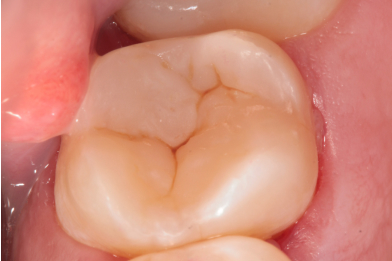

Лечение кариеса 1.7 зуба. Препарирование кариозной полости. Восстановление анатомо-физиологической формы с использованием пломбировочного материала.

Бояринов Сергей Эдуардович -